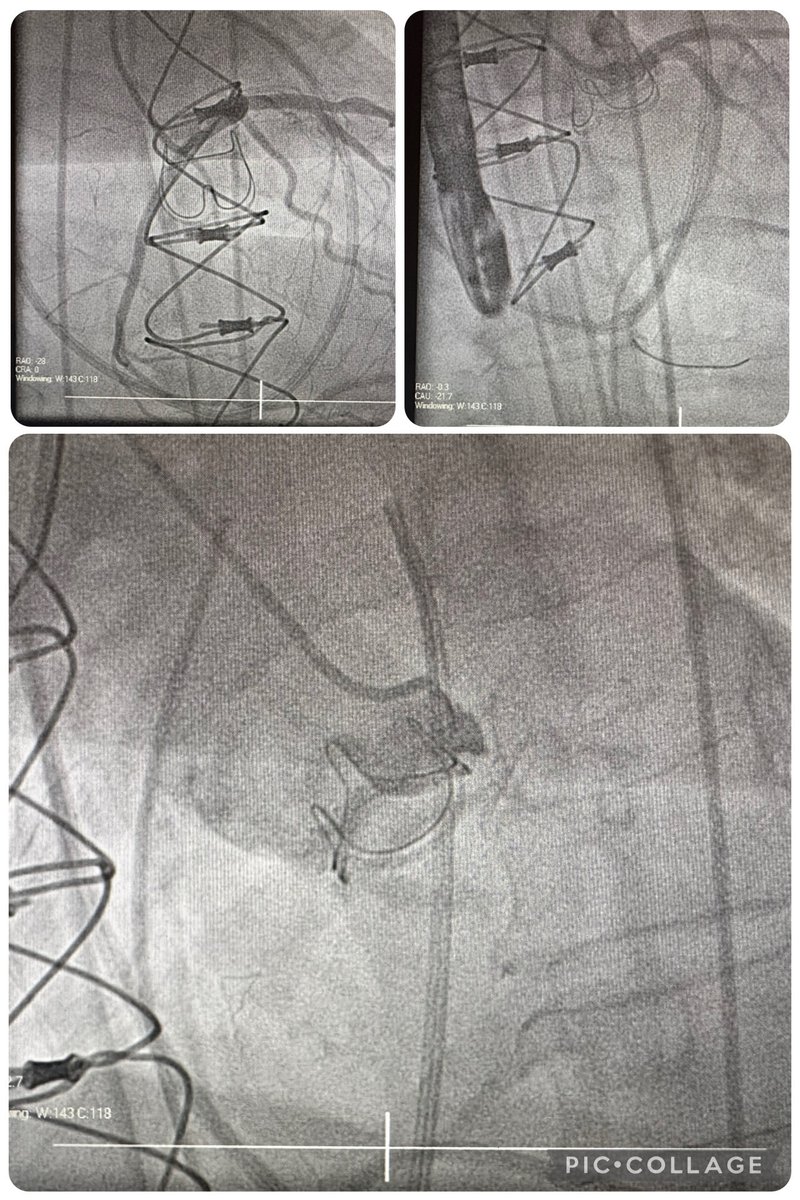

69 y/o, LIMA and SVGs occluded. 2 previous LAD stents (before CABG). Stable angina CCS 3. RRA, 7F, JL 3.5. Mini-crush technique. #Radialfirst #leftmainpci #PCI #interventionalcardiology #radial